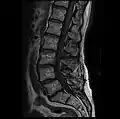

MRI lumbar spine with degeneration, post-hemilaminectomy L4-5 (sagittal T1 FSE)